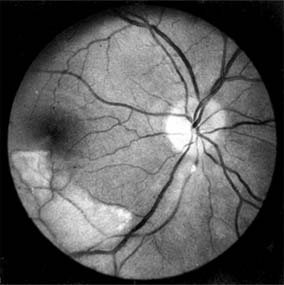

Red-free light (a white light with a green filter) allows details of hemorrhages, focal irregularity of blood vessels, and nerve fibers to be seen more clearly (Figure 15-9).

Figure 15-9

Figure 15-9: Acute retinal infarction. Red-free photograph shows acute arterial occlusion in a congenitally anomalous vessel at the disk. The inferior retina is infarcted, but axoplasm has accumulated beneath the fovea in an irregular pattern owing to preserved neuronal function of the distal ganglion cells.